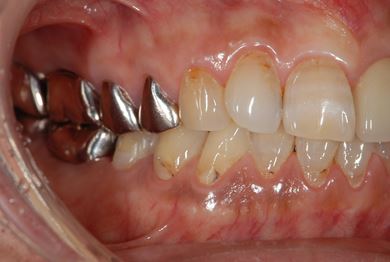

| 性別/年齢 | 男性 / 69歳 | ||||||||||||||||||||||||||||||||

| 主訴 | 1.左上奥歯の詰め物が取れた 2.左上前歯の欠け 3.右下奥歯の欠け | ||||||||||||||||||||||||||||||||

| 治療方針 | セラミック治療にて、審美的回復を行う。 | ||||||||||||||||||||||||||||||||

| 治療内容 | メタルボンドセラミッククラウン1本(メタルボンド用土台1本)、ハイブリッドセラミックインレー1本 | ||||||||||||||||||||||||||||||||

| 総治療費 | 172,410円 | ||||||||||||||||||||||||||||||||

| 治療期間 | 4ヶ月 |